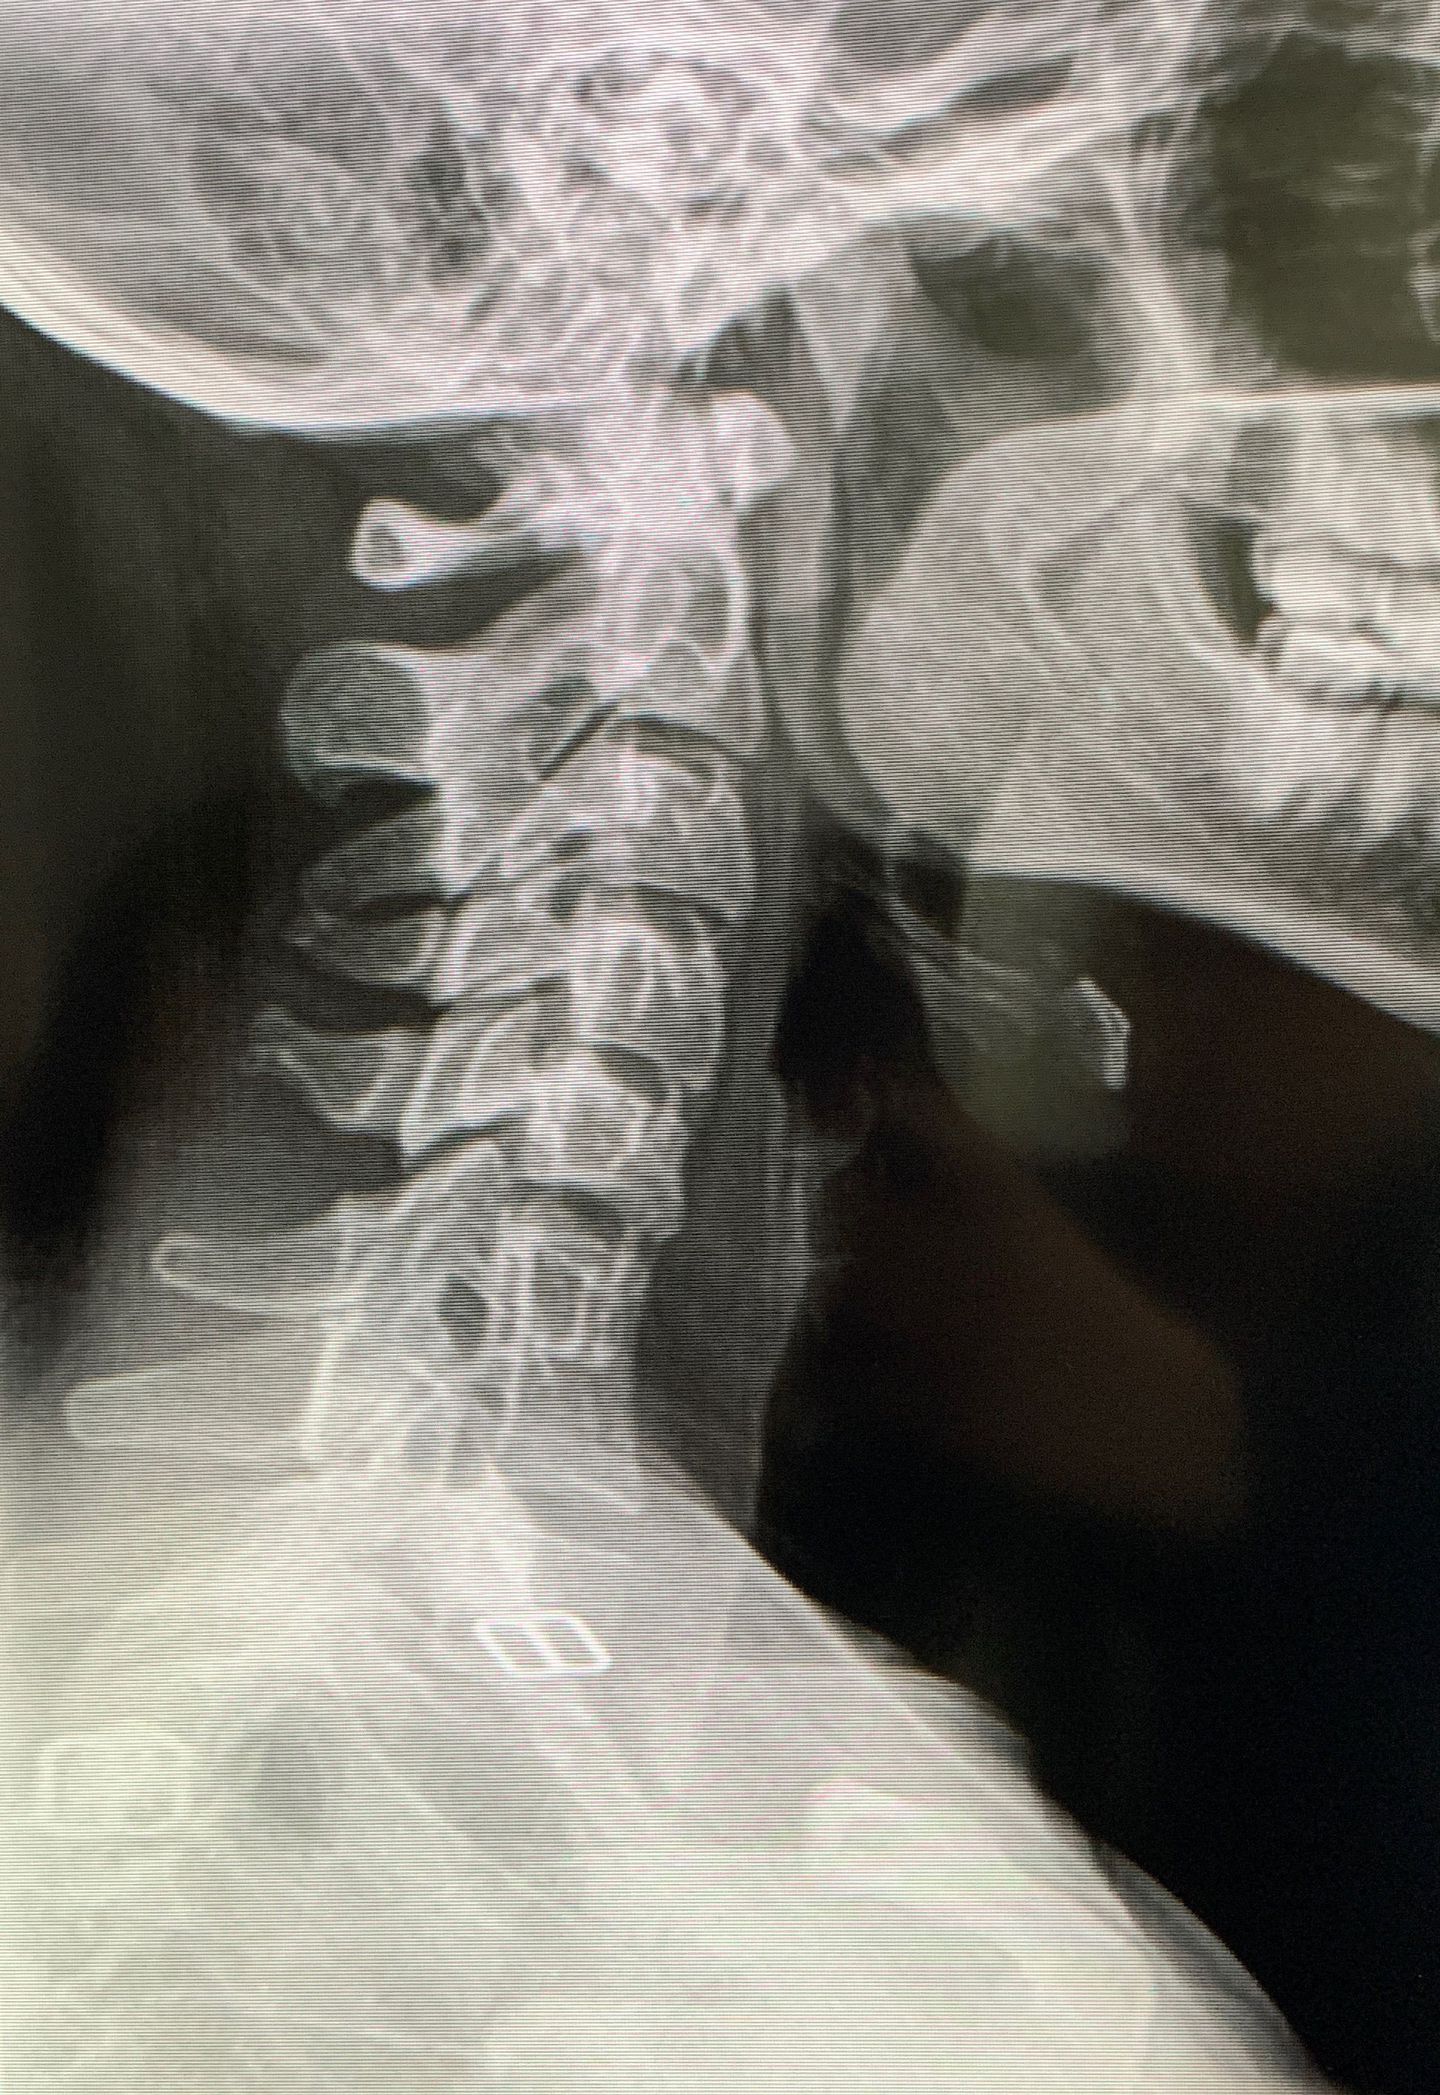

Patient is a 20 year old female, diagnosed with Ehlers Danlos syndrome at age of 19, previous diagnosed with amplified musculoskeletal pain syndrome at age 16, MD suggested yoga, Acupunture, and talk therapy to relieve pain, saw no results only worsen physical pain. Patient saw chiropractor 1 month ago and this X-ray was taken. Patient has been experiencing neck pain 7/10 everyday.

1-Locked Facet between C5 and C6 2- Congenital fusion of C2 and C3 3-Fusion between C6 and C7